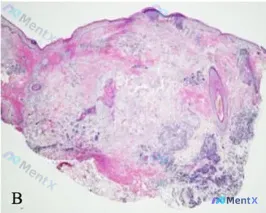

整理到一份皮肤活检的读片材料,感觉有点“陷阱感”,先放出来大家看看思路会不会走偏。 已知背景: 这份是“基线期转移灶”的皮肤活检H&E染色。 形态学表现(整理自材料): - 真皮层可见密集淋巴细胞浸润,以中深层为主,有向深部延伸趋势 - 血管扩张+血管周围袖口样浸润 - 同时有肿瘤细胞完全位于真皮层...